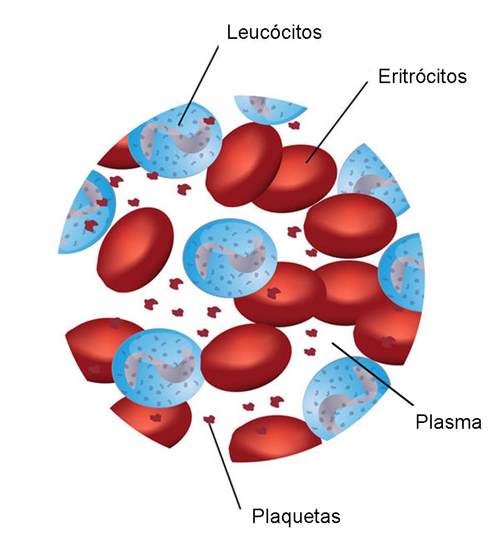

O sangue é constituído por uma porção líquida – o plasma – e por células com funções diferentes – hemácias, leucócitos e plaquetas (figura 1).

Figura 1 – Representação de uma observação ao microscópio dos constituintes do sangue.

O plasma é composto por água, iões, nutrientes, proteínas e outras moléculas, tais como hormonas não proteicas, e resíduos do metabolismo. O plasma desempenha diversas funções, como transporte de moléculas, manutenção da pressão osmótica e coagulação.

As hemácias, também denominadas de glóbulos vermelhos ou eritrócitos, são células sem núcleo (anucleadas), em forma de disco e com um tempo médio de vida de 120 dias. Estas células contêm hemoglobina, uma proteína que confere a cor vermelha ao sangue. A função das hemácias é o transporte de gases (oxigénio e dióxido de carbono).

Os leucócitos ou glóbulos brancos são células nucleadas, responsáveis pela resposta imunitária, isto é, pela defesa do organismo contra agentes patogénicos, potencialmente causadores de doença. A estrutura e as características químicas dos leucócitos permitem agrupá-los em duas categorias principais: granulócitos e agranulócitos. Os granulócitos contêm grânulos específicos no citoplasma e incluem os neutrófilos, os eosinófilos e os basófilos. Os agranulócitos não possuem grânulos específicos no citoplasma e incluem os linfócitos e os monócitos.

As plaquetas sanguíneas ou trombócitos são fragmentos celulares muito pequenos resultantes de megacariócitos (células gigantes polinucleadas presentes na medula óssea e envolvidas no processo de produção dos elementos celulares que compõem o sangue). As plaquetas são responsáveis pela coagulação do sangue, impedindo ou bloqueando hemorragias.